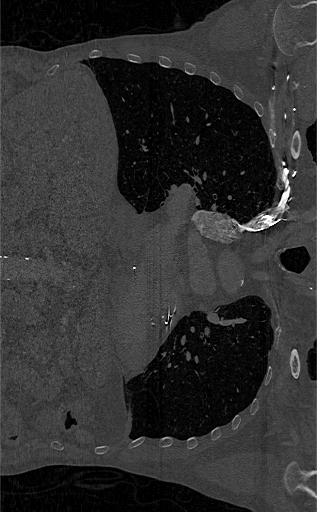

View the 2-D slices using the imshow function.

figure

imshow(XZ,[],Border="tight")